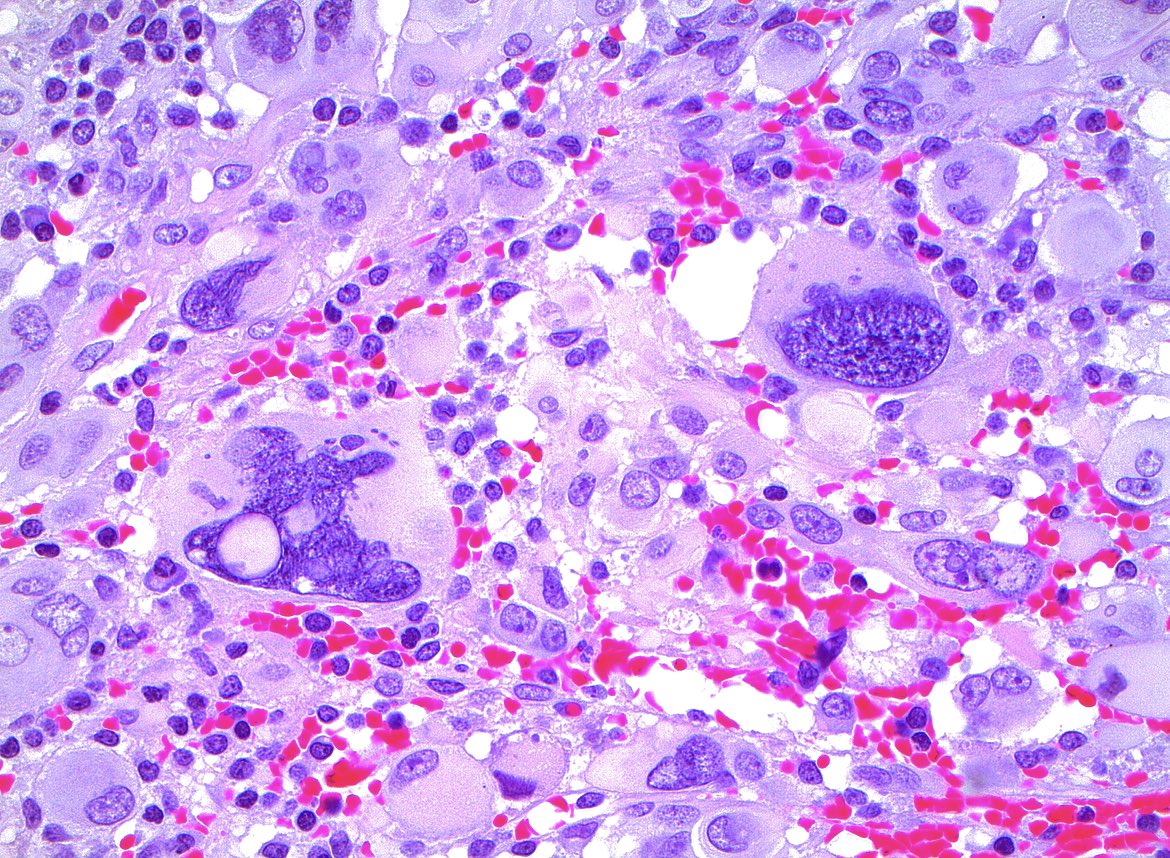

🔬 The second paper from our new Practice Essentials series is now available! This edition, led by Manon Auger MD of @mcgillu, presents a practical approach to follicular neoplasm (FN) and its subtype oncocytic FN. acsjournals.onlinelibrary.wiley.com/doi/full/10.10… #CytoPath #ENTPath #BethesdaSystem